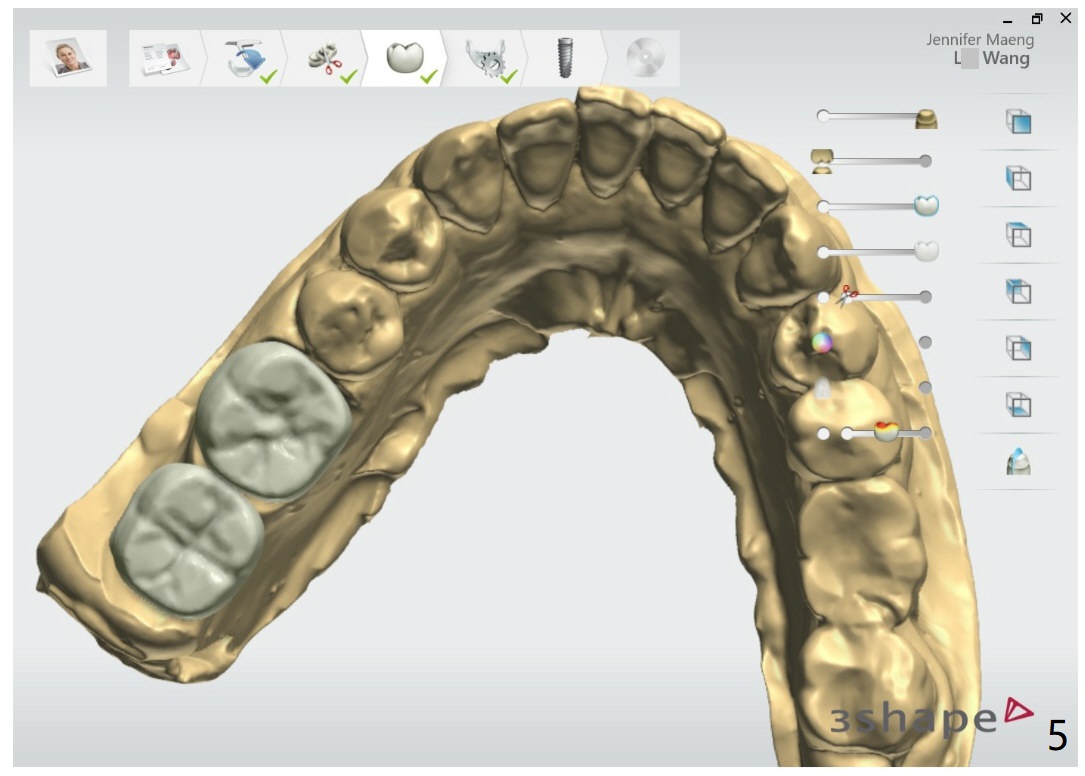

Limited Vertical Space

Return to Lower Molar Immediate Implant, Trajectory II